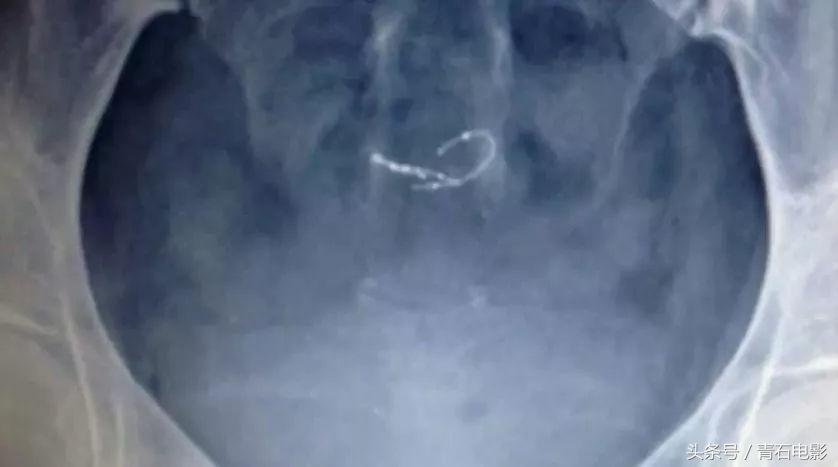

Essure由一个微小的四公分线圈组成,通过子宫插入并放置在输卵管内。

它的工作原理是:刻意造成输卵管的发炎反应,以形成结痂组织。

然后结痂组织会永久性的关闭输卵管。

伴随着腹部左侧的尖锐刺痛感越来越强烈,A去医院做了超声波检查。

结果发现:Essure已经由输卵管跑到了子宫里。

而如此严重的并发症,仅仅是由一个不足四公分的线圈引起的。